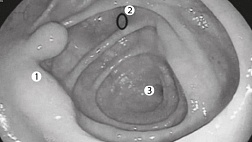

В просвете желудка вязкий секрет, плохо отмывается от стенок. Слизистая в теле отечна, с умеренной гиперемией. В антральном отделе гипертрофированные складки на верхушках эрозированные очаги с признаками эпителизации. Складки во всех отделах желудка при инсуффляции расправляются полностью, в дистальных отделах отсутвуют коллекторные венулы. Перистальтика симметричная. Привратник овальной формы, не смыкается . Дуоденогастральный рефлюкса нет .В инверсии кардия охватывает аппарат в виде "купола".

12-кишка: Просвет луковицы двенадцатиперстной кишки обычный, содержит небольшое количество желчи, перистальтика активная , слизистая оболочка розового цвета, ворсинки сохранены. Так же прослеживаются пигментированные образования от 2мм до 8мм. серо-синюшного оттенка. Постбульбарном отделе множественные пигментые образования до 10мм, единичные кратообразные пигментные образования до 15мм, глубиной до 5мм., дно покрыто серым фибрином. Биопсия 2-а кусочка.

Заключение: ГПОД. Грыжевая гастропатия. Эрозивная гастропатия антрального отдела желудка. MTS Меланома ЛДПК, залуковичного отдела. Биопсия.